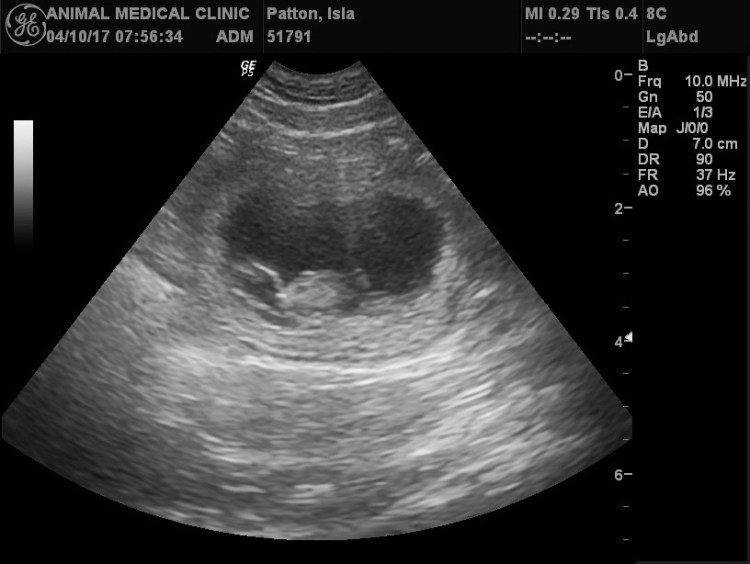

We took Isla in for an ultrasound today, and we saw some rambunctious puppies in her belly! It will be a good sized litter, so we’re starting reservations now. Puppies coming mid-May!